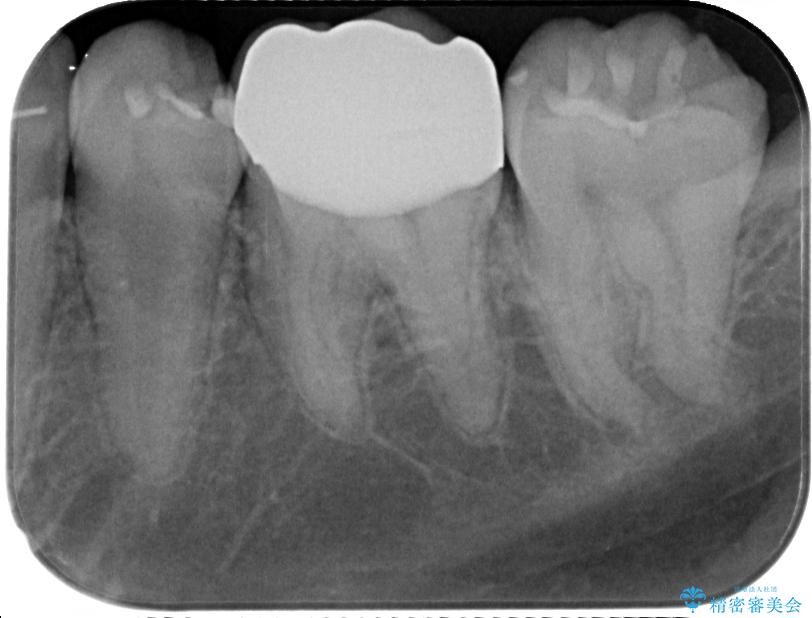

- 当院で矯正治療を終えて、左下が虫歯になっている気がするとのことで来院された患者様です。レントゲン検査の結果、コンポジットレジンによる修復箇所が複数行われており、詰め物の下に虫歯を認めました。

拡大鏡視野下でコンポジットレジン、虫歯の除去を行い、オールセラミッククラウンに適した形に整えました。